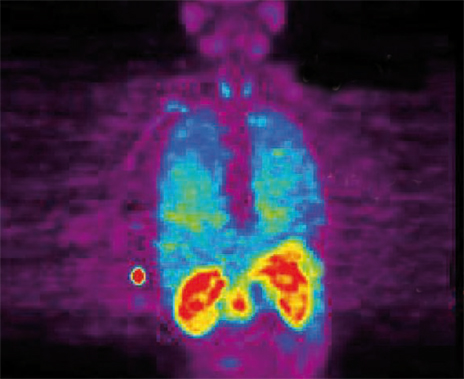

Un scanner mais pas seulement ! La Tomographie par Émission de Positons couplée au scanner, autrement dit le TEP-Scan (PET-Scan chez les anglosaxons), utilise le rayonnement d’un marqueur capté par une caméra, le tout effectué dans un scanner. Cette imagerie est de plus en plus utilisée dans le dépistage précoce des cancers.

On connaissait le scanner «classique», puis le scanner dit « hélicoïdal ». Voici venu depuis quelques années le TEP-Scan, un examen que les concepteurs n’hésitent pas à qualifier de révolutionnaire. Cette imagerie n’est pourtant pas nouvelle. Les principes physiques qui la régissent datent des années 50 et les premières images remontent à 1957. Elle s’est affirmée à la fin des années 80 dans le domaine de la cancérologie. Le TEP-Scan permet de repérer des tumeurs de l’ordre de 8 mm de diamètre. Cette imagerie permettrait donc de déceler des tumeurs insoupçonnées ou difficilement visibles par les autres techniques d’investigations.

Le 18FDG va être capté par des cellules hyperactives avides de sucre : les cellules cancéreuses par exemple. La réaction est captée par une caméra à positons située dans un scanner qui lui, construit l’image anatomique captée par la caméra.

Le TEP-Scan concerne le fonctionnement cellulaire et plus seulement l’aspect morphologique des organes. Il permet d’évaluer presque en temps réel l’efficacité d’une chimiothérapie en montrant l’évolution de la tumeur. Le TEP-Scan fournit des images en trois dimensions en coupe de 3 à 4 mm d’épaisseur.

À chaque type de cancer recherché correspond l’usage d’un type de fluor particulier permettant donc un dépistage « personnalisé » de la tumeur, et ce, de façon précoce. Le TEPScan cible tout particulièrement le cancer du poumon, du côlon, de la peau (mélanome), de l’oropharynx, des ovaires, des seins, de la thyroïde, de l’oesophage ou du cerveau. Le TEP-Scan est utilisé également dans le diagnostic précoce de la sarcoïdose, dans le diagnostic des fièvres persistantes d’origine inconnue, dans les pathologies vasculaires inflammatoires ou infectieuses rachidiennes. On parle aussi d’applications dans la recherche des séquelles cardiaques après un infarctus (recherche de la viabilité du muscle cardiaque), dans l’épilepsie à forme temporale et dans les maladies d’Alzheimer et de Parkinson.